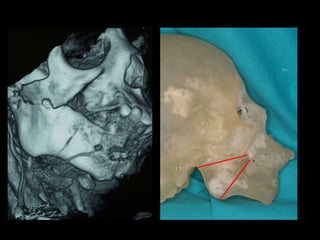

Mandíbula  sin  relación céntrica Técnica en  espejo Reconstrucción  2ª

Adquisición de datos Reconstrucción virtual del modelo 3D Técnica de espejo Validación Validación Producción física del modelo Cirugía de modelo: moldeo placa, osteotomía mandíbula y peroné. Esterilización: placa y sistema y modelo Uso en quirófano

Concepto de modelo en espejo

Ingletes: guías de corte

Moldeado previo de la placa